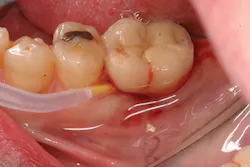

Late implant complications occur after the implant has integrated and the final prosthesis has been placed. Recognition of these complications via radiographic and clinical analysis is extremely important since many of these problems can be corrected if detected early. On the other hand, if allowed to progress, a minor complication can often result in loss of the implant and/or prosthesis. Late complications of the dental implant fall into the category of biologic or mechanical complications. Late biologic complications are those in which the peri-implant soft and hard tissues are affected. Peri-implant mucositis describes a reversible inflammatory reaction in the mucosa adjacent to an implant,(8) a term that has become known as implant gingivitis. Studies show that the prevalence of peri-implant mucositis can be as high as 50% to 80% of implants in function(9) with the etiology of peri-implant mucositis being bacterial plaque. Typical clinical presentation includes erythema, edema, swelling, and redness (Figs. 1 and 1a). Although bleeding upon probing and increased probing depths are not always indicative of peri-implant mucositis,(10) the absence of these two factors usually means implant health.(11)